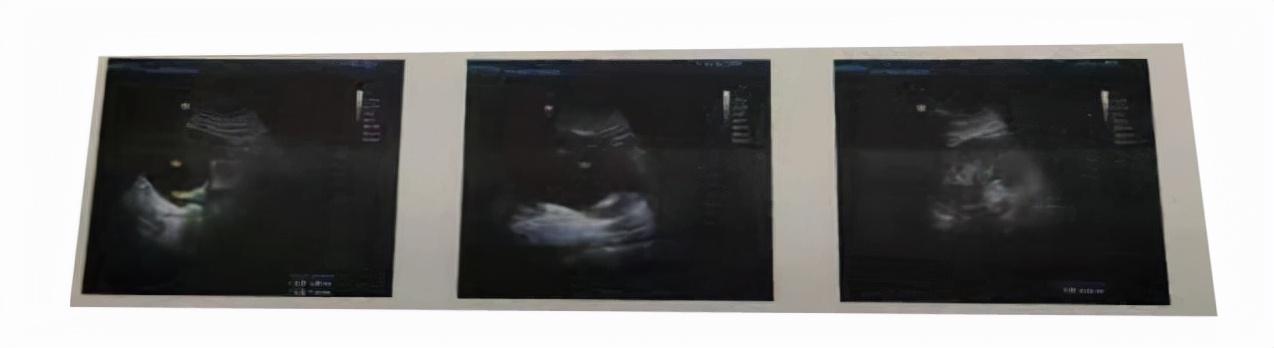

入院后,除了完善血常规、尿常规、凝血、传染病四项等检查外,同时完善了CT、超声检查,其中尿液检查提示肌酐正常,尿酸轻度升高,超声提示左肾形态大小正常,实质回声均匀,右肾体积增大,轮廓尚清晰,实质回声变薄,其内可见大片液性暗区,右侧输尿管上端扩张,于右肾肾盂出口处见一直径约20mm强光团,提示右侧肾脏功能基本已经丧失,右侧输尿管结石。

六、医生感悟